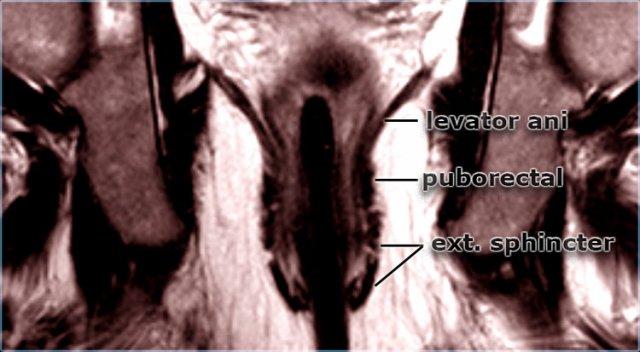

Trên các hình ảnh MRI mặt phẳng axial và coronal, các lớp khác nhau của cơ thắt hậu môn cùng các cấu trúc xung quanh có thể được hiển thị một cách rõ nét và chi tiết.

Cơ thắt hậu môn bao gồm ba lớp:

- Cơ thắt trong: là phần tiếp nối của lớp cơ trơn vòng của trực tràng, hoạt động không tự chủ, co lại khi nghỉ ngơi và giãn ra khi đại tiện.

- Khoang liên cơ thắt.

Cơ thắt ngoài: cơ vân hoạt động tự chủ, được chia thành ba lớp hoạt động như một đơn vị thống nhất.

Ba lớp này liên tục với cơ mu-trực tràng và cơ nâng hậu môn ở phía trên (hình minh họa).

Cơ mu-trực tràng có nguyên ủy từ hai bên khớp mu, tạo thành một ‘vòng đai’ bao quanh vùng trực tràng-hậu môn.

Cơ mu-trực tràng co lại khi nghỉ ngơi và tạo ra góc gập 80° tại vùng nối trực tràng-hậu môn.

Cơ này giãn ra trong quá trình đại tiện.